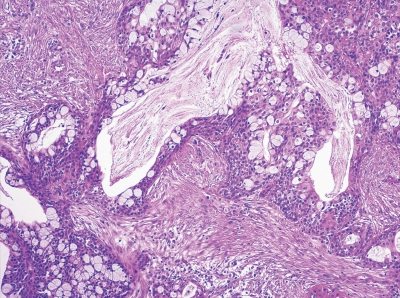

25歳の女性。右側口蓋部の無痛性腫脹を主訴として来院した。1年前から軽度の腫脹に気付いていたがそのままにしていたところ、最近徐々に増大したという。同部に波動や圧痛はない。初診時の口腔内写真、CT、MRI T2強調像及び生検時のH-E染色病理組織像を示す。

診断名はどれか。1つ選べ。

b. 多形腺腫